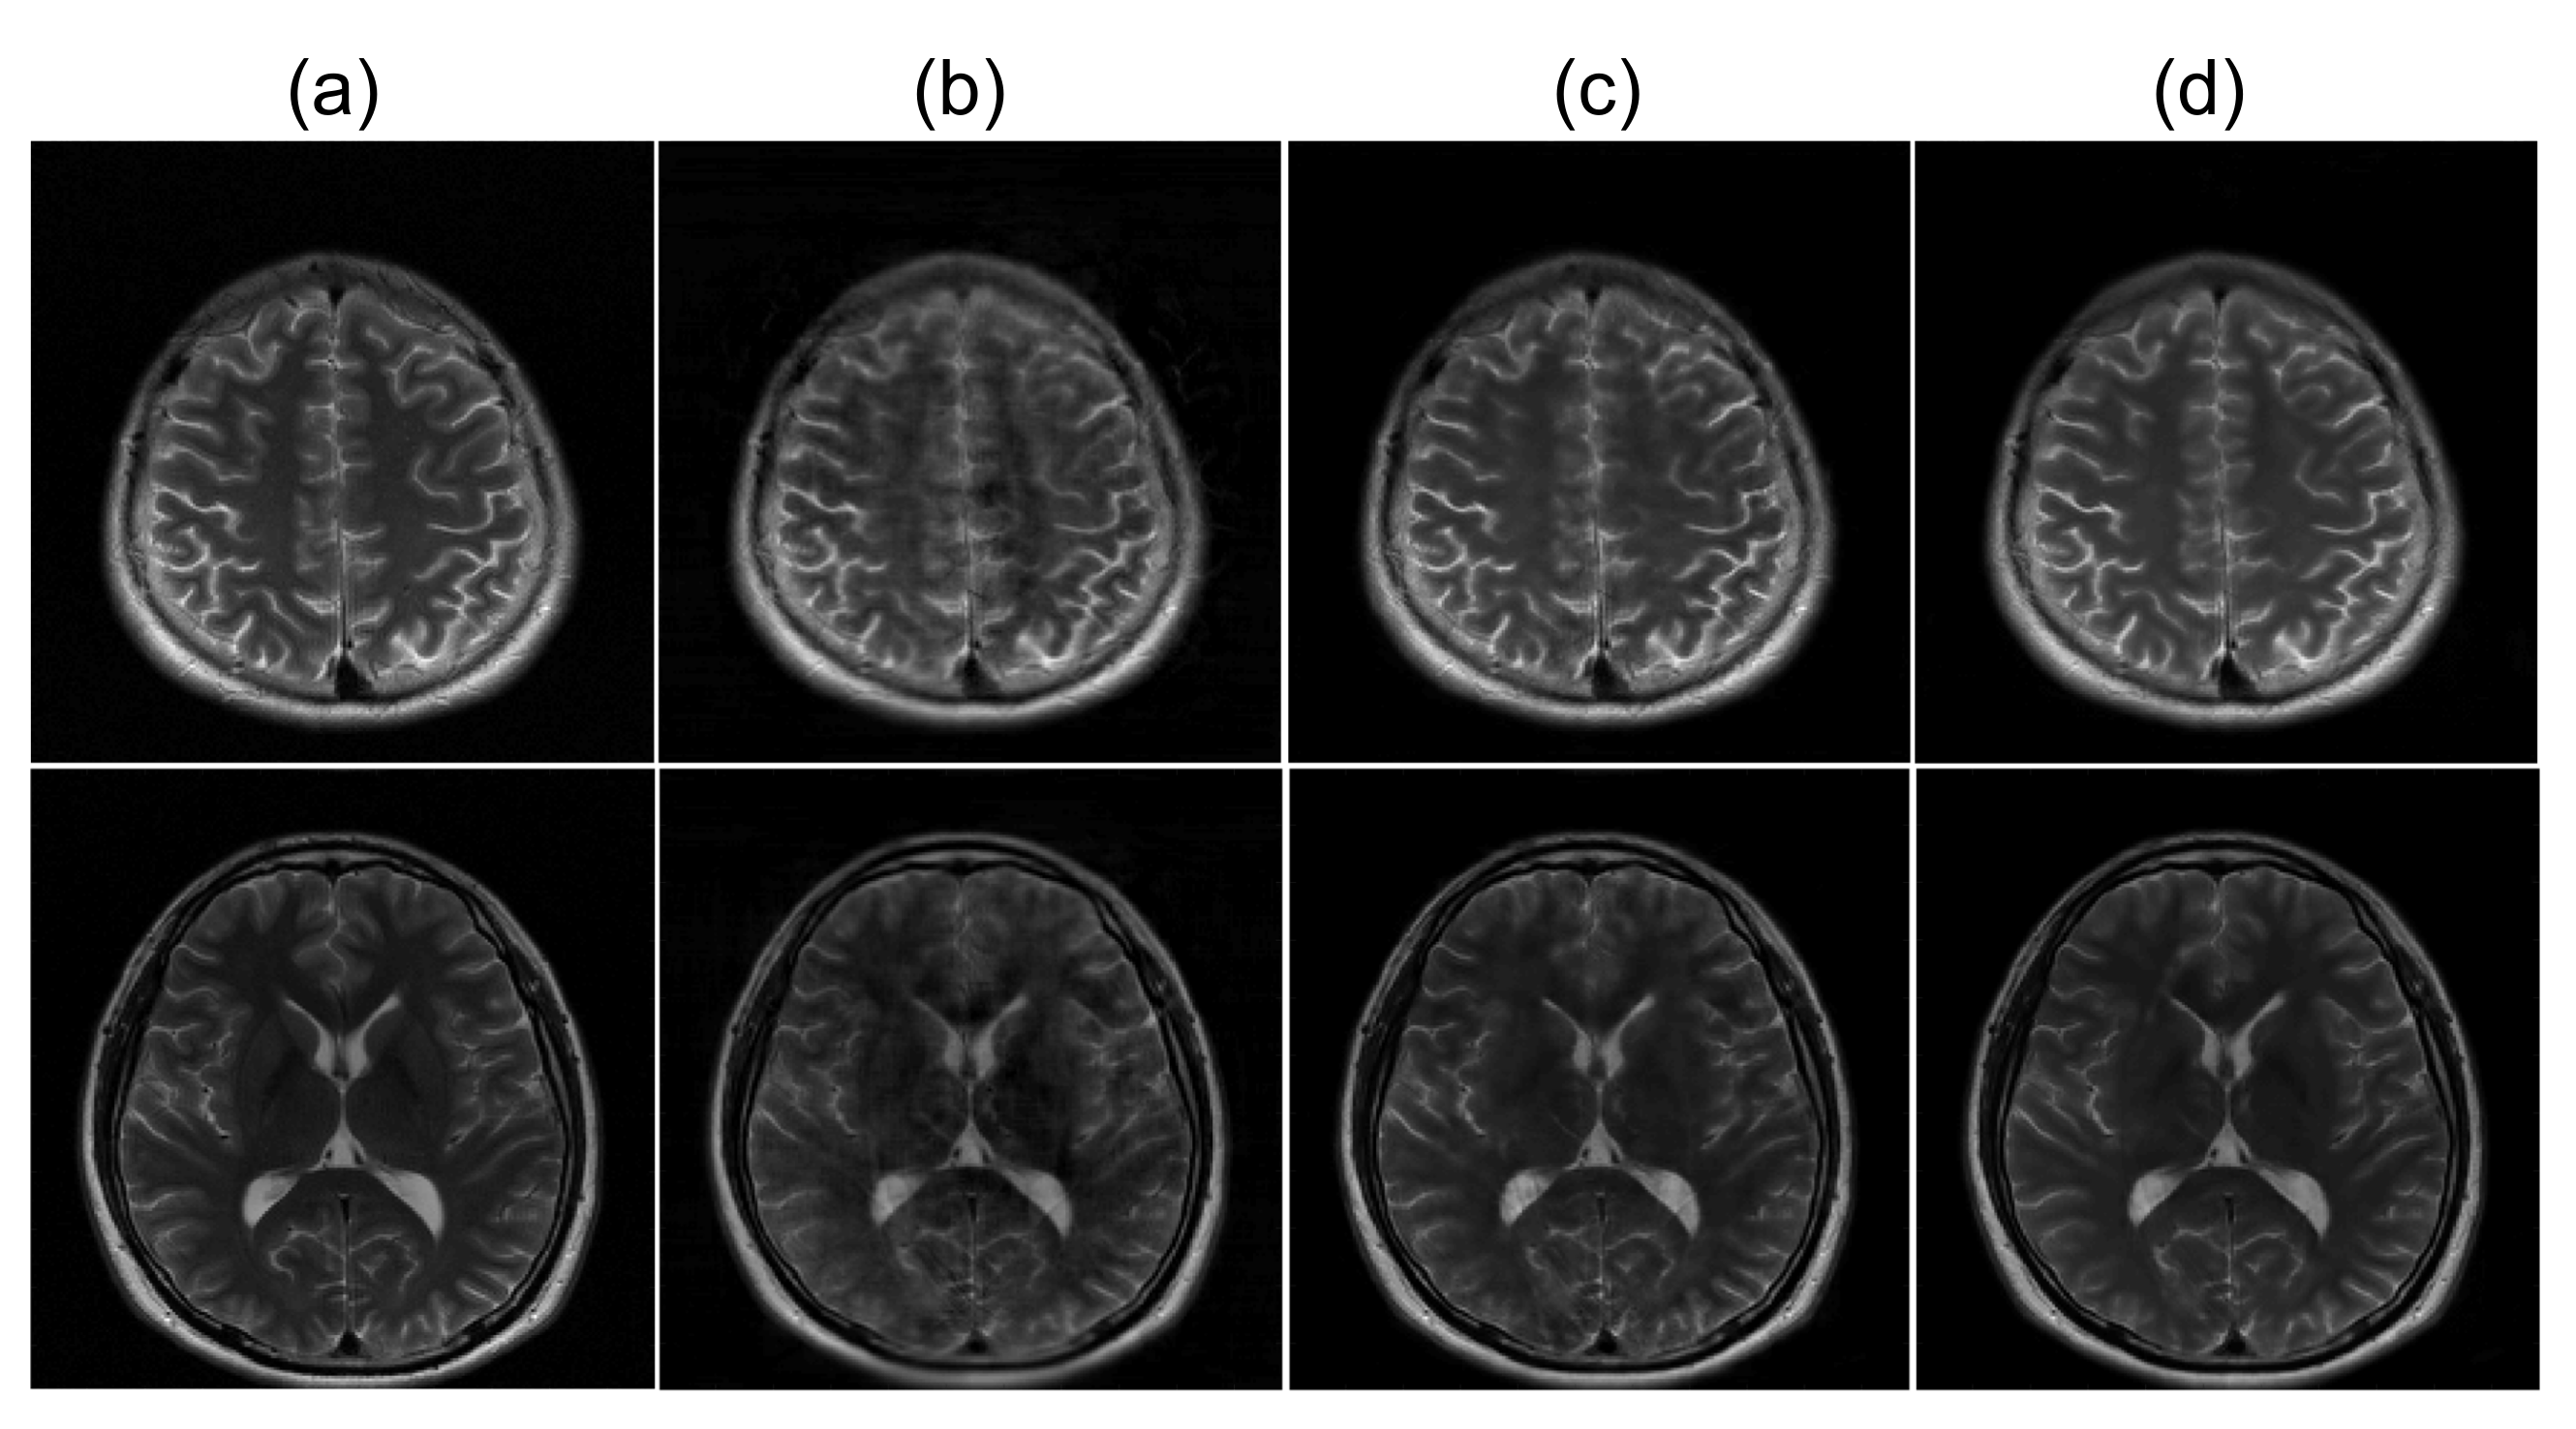

Figure 4 presents the reconstructed images from three different refinement networks: the single convolution layer, multiple convolutional layers, and dual frame U-net. Figure 5 presents the quantitative analysis of the three refinement networks. As shown in Figure 4, the images refined by the single convolution layer contain a substantial amount of structural artifacts. In addition, the image details are also deteriorated. In contrast, the images refined by the WTA and DFU have considerably improved image quality, and the image details are clear. However, the images refined by the DFU have better image details. The quantitative measures also demonstrate that the DFU can be efficiently used for the refinement of the latent features in the proposed method. The single convolutional layer shows considerably higher nMSE and lower SSIM values than the other two methods, and the DFU shows improved performance in terms of nMSE and SSIM.

Figure 4.

Comparison of three different refinement networks (Section 4.1). Two example slices of experiment results are shown. (a): Ground truth magnitude images (label images). (b–d): Reconstructed images using (b) single convolutional layer, (c) WTA, and (d) DFU.